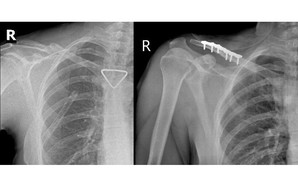

Giữ thang giúp hàng xóm, người đàn ông bị bỏng điện kinh hoàng

(NLĐO) - Bỏng điện do nổ hồ quang là tai nạn hiếm gặp nhưng cực kỳ nguy hiểm, có thể gây tổn thương sâu, lan rộng và đe dọa tính mạng chỉ trong tích tắc.